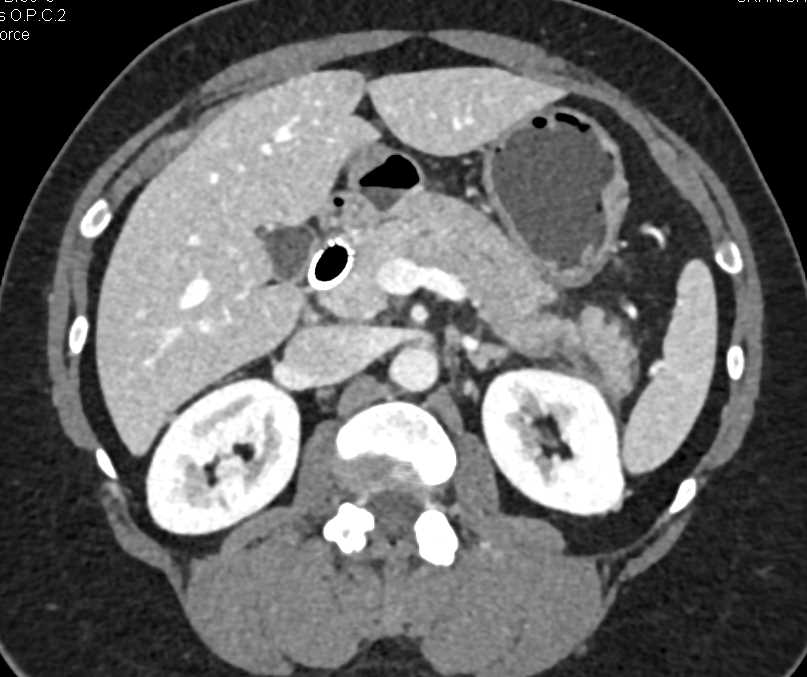

Pelvic Congestion Syndrome with Huge Pelvic Varices and Collaterals